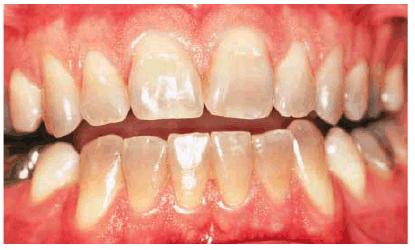

Tetracycline is considered one of the most difficult tooth stains to remove.

In-office bleaching is a possible treatment method but generally is

contraindicated due to the number of treatments required and the concurrent

high fee and patient discomfort. With the advent of at-home bleaching, these

tetracycline stains can be managed more easily.49,51,60 Treatment

times may vary from 2 months to 1 year (Figures 16-28A 16-28B 16-28C 16-29A 16-29B 16-30A 16-30B 16-31A, and 16-31B). Patients are seen monthly to

replenish solutions and evaluate for continuing color change. Patients should

agree to a minimum of 2 months of nightly treatment before deciding to proceed

to more aggressive treatment. Fees are generally the cost of a monthly office

recall visit and additional material. Once lightening is observed, patients

should continue treatment until a month has passed with no obvious color

change. Dark tetracycline stains located in the gingival third of the tooth or

dark blue or gray stains have the least favorable prognosis. However, even in

these situations, there can be some improvement. This improvement may be

sufficient for the patient's esthetic demands. However, compliance by the

patient is necessary for success. Patients with tetracycline staining often

Figure 16-29A: Moderately tetracycline-stained teeth.

Figure 16-29B: In a research study, these teeth were bleached for 6 months nightly with a 10% carbamide peroxide. Not all results will be this good, especially if the discoloration is blue/gray or at the gingival third.